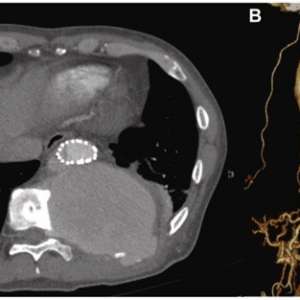

Мужчина, 59 лет

Обратился в отделение неотложной помощи с жалобами на постепенно усиливающуюся боль в спине, которая беспокоила его в течение месяца.

В анамнезе травма грудного отдела позвоночника, полученная в возрасте 42 лет, которая привела к параплегии нижних конечностей и потребовала установки позвоночной пластины. В возрасте 45 лет ему была проведена экстренная операция TEVAR по поводу разрыва инфицированной аневризмы нисходящей части грудной аорты с использованием одностентного трансплантата Najuta (Kawasumi Labo, Inc., Токио, Япония), который состоит из Z-образного стента и ткани из политетрафторэтилена (ПТФЭ). Проведена антибиотикотерапия.

После выздоровления пациент находился под наблюдением в амбулаторных условиях. В течение периода наблюдения его артериальное давление поддерживалось на уровне примерно 130 мм рт. ст. без эпизодов тяжелой гипертензии.

На момент обращения гемодинамические показатели пациента были стабильными: артериальное давление составляло 140/95 мм рт. ст., а частота сердечных сокращений — 110 ударов в минуту.

При осмотре была обнаружена пульсирующая опухоль, пальпируемая примерно на расстоянии трёх пальцев ниже кончика левой лопатки.

📌 Из-за изменений в алгоритмах ВКонтакте мы вынуждены публиковать только анонсы.

Обратился в отделение неотложной помощи с жалобами на постепенно усиливающуюся боль в спине, которая беспокоила его в течение месяца.

В анамнезе травма грудного отдела позвоночника, полученная в возрасте 42 лет, которая привела к параплегии нижних конечностей и потребовала установки позвоночной пластины. В возрасте 45 лет ему была проведена экстренная операция TEVAR по поводу разрыва инфицированной аневризмы нисходящей части грудной аорты с использованием одностентного трансплантата Najuta (Kawasumi Labo, Inc., Токио, Япония), который состоит из Z-образного стента и ткани из политетрафторэтилена (ПТФЭ). Проведена антибиотикотерапия.

После выздоровления пациент находился под наблюдением в амбулаторных условиях. В течение периода наблюдения его артериальное давление поддерживалось на уровне примерно 130 мм рт. ст. без эпизодов тяжелой гипертензии.

На момент обращения гемодинамические показатели пациента были стабильными: артериальное давление составляло 140/95 мм рт. ст., а частота сердечных сокращений — 110 ударов в минуту.

При осмотре была обнаружена пульсирующая опухоль, пальпируемая примерно на расстоянии трёх пальцев ниже кончика левой лопатки.